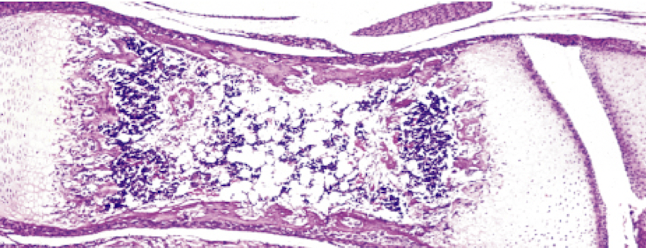

What is a mixed spicule?

A transition area that possesses both cartilage and bone

Mixed spicule labeled components

ID

Mixed spicule